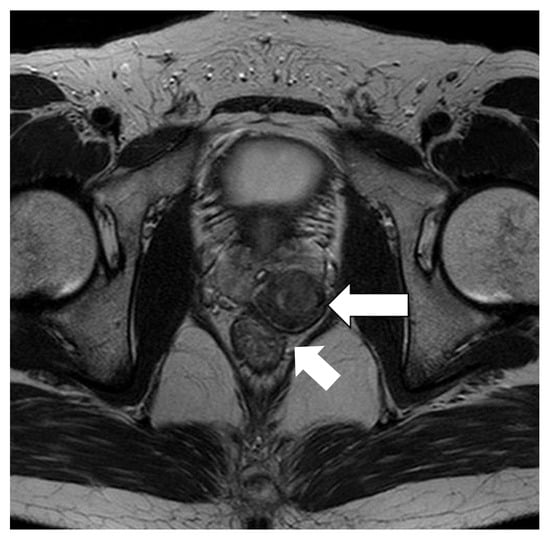

2. Case Report